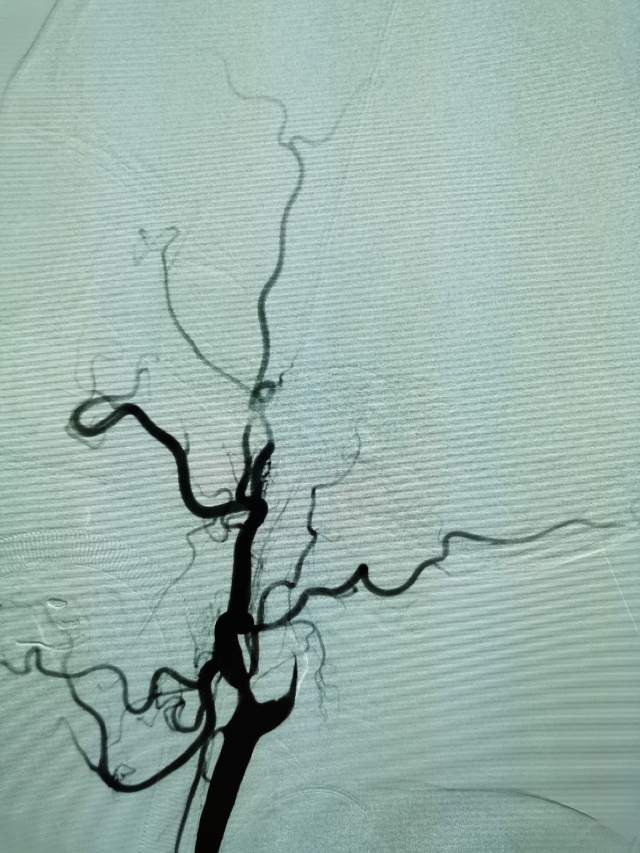

我们全面评估后,基于安全考虑,住院期间先后完成了两次外科干预,帮助患者将已经闭塞的血管重新开通,“满江红”的大脑终于变成了“半江红”,第一次外科干预后,保姆说改变好明显;第二次干预后的第二天,患者眼神明亮、对答如流、思维敏捷、面带微笑,在病房里走来走去,俨然像巡视病房的医生,很是拉风。